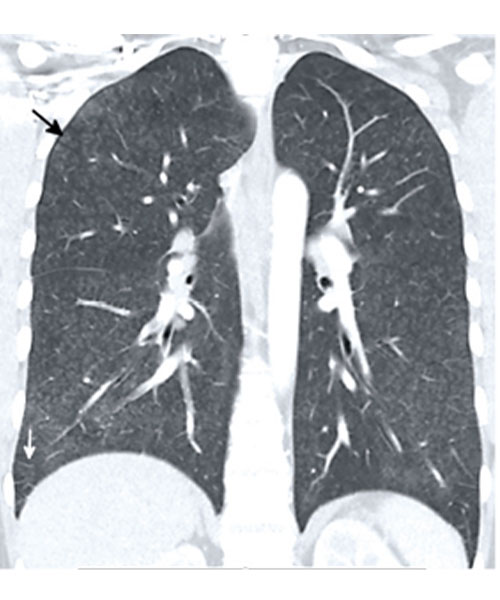

22-year-old man with fever, abdominal pain, and dyspnea presents to the emergency department in August 2021. Coronal CT image shows diffuse hazy centrilobular nodules (black arrows) and mild septal thickening (white arrows). The heart (not shown) was normal. The imaging pattern is consistent with an airway-centered organizing pneumonia pattern of EVALI, which was suggested based on the imaging findings. The patient admitted to daily vaping of THC with his symptoms developing after purchasing a new vape pen two days before admission from a legal vape shop in California. While diffuse centrilobular nodules can also be seen with excipient lung disease, the nodules in excipient lung disease and smaller and well-defined and right heart strain is also often present.

Courtesy of Chest Journal: Kligerman et al, 2021; 160:1492-1511